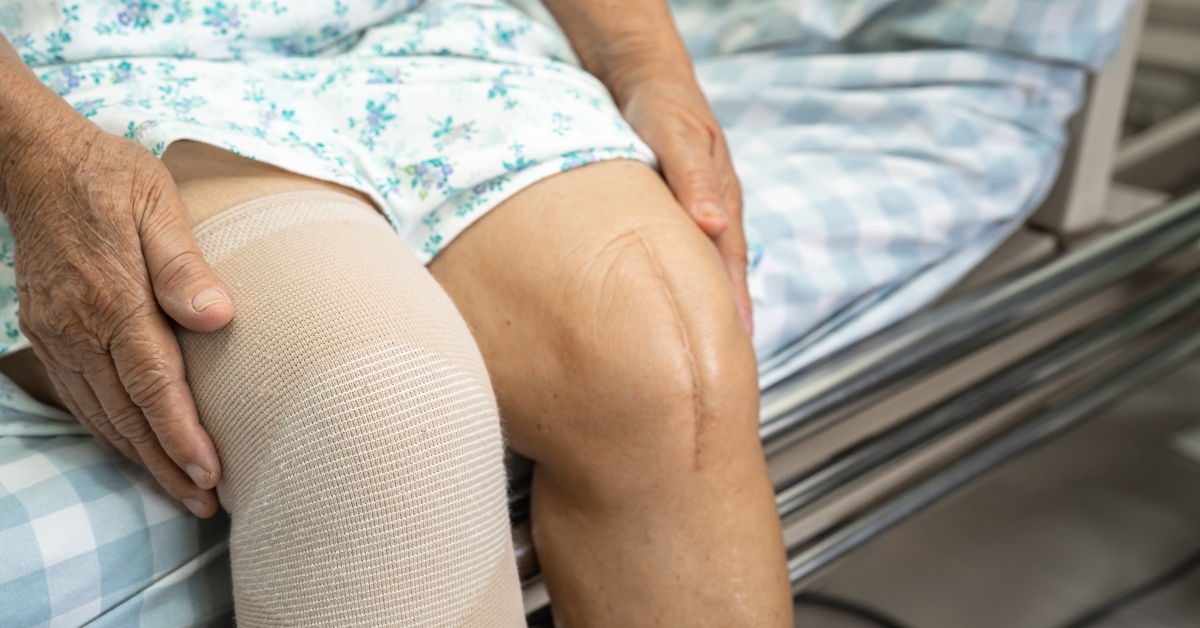

関節の変形が進んだ場合は手術を検討する事になります。(「標準整形外科学」 医学書院)

軟骨の摩耗が進んでしまうと、これを自然に戻す方法はないため、人工関節に入れ替える手術を行います。

膝の前面には大きな手術跡が残るし、可動域も自然な膝より悪くなります。(人工関節の種類によって変動します)

新しい膝(人工関節)にすれば完全に元の生活に戻れるかといえば、決してそうではありません。

正座など膝に負担のかかる姿勢・動作や、過度な運動は制限されます。